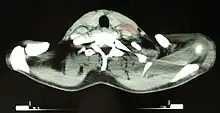

Diagnosis

Hodgkin lymphoma must be distinguished from noncancerous causes of lymph node swelling (such as various infections) and from other types of cancer. Definitive diagnosis is by lymph node biopsy (usually excisional biopsy with microscopic examination). Blood tests are also performed to assess function of major organs and safety for chemotherapy.[22] Positron emission tomography (PET) is used to detect small deposits that do not show on CT scanning. PET scans are also useful in functional imaging (by using a radiolabeled glucose to image tissues of high metabolism). In some cases, a gallium scan may be used instead of a PET scan.[23]

After Hodgkin lymphoma is diagnosed, a person will be staged: that is, they will undergo a series of tests and procedures that will determine what areas of the body are affected. These procedures may include documentation of their histology, a physical examination, blood tests, chest X-ray radiographs, computed tomography (CT)/positron emission tomography (PET)/magnetic resonance imaging (MRI) scans of the chest, abdomen and pelvis, and usually a bone marrow biopsy. PET scan is now used instead of the gallium scan for staging. On the PET scan, sites involved with lymphoma light up very brightly enabling accurate and reproducible imaging.[35] In the past, a lymphangiogram or surgical laparotomy (which involves opening the abdominal cavity and visually inspecting for tumors) were performed. Lymphangiograms or laparotomies are very rarely performed, having been supplanted by improvements in imaging with the CT scan and PET scan.[18]